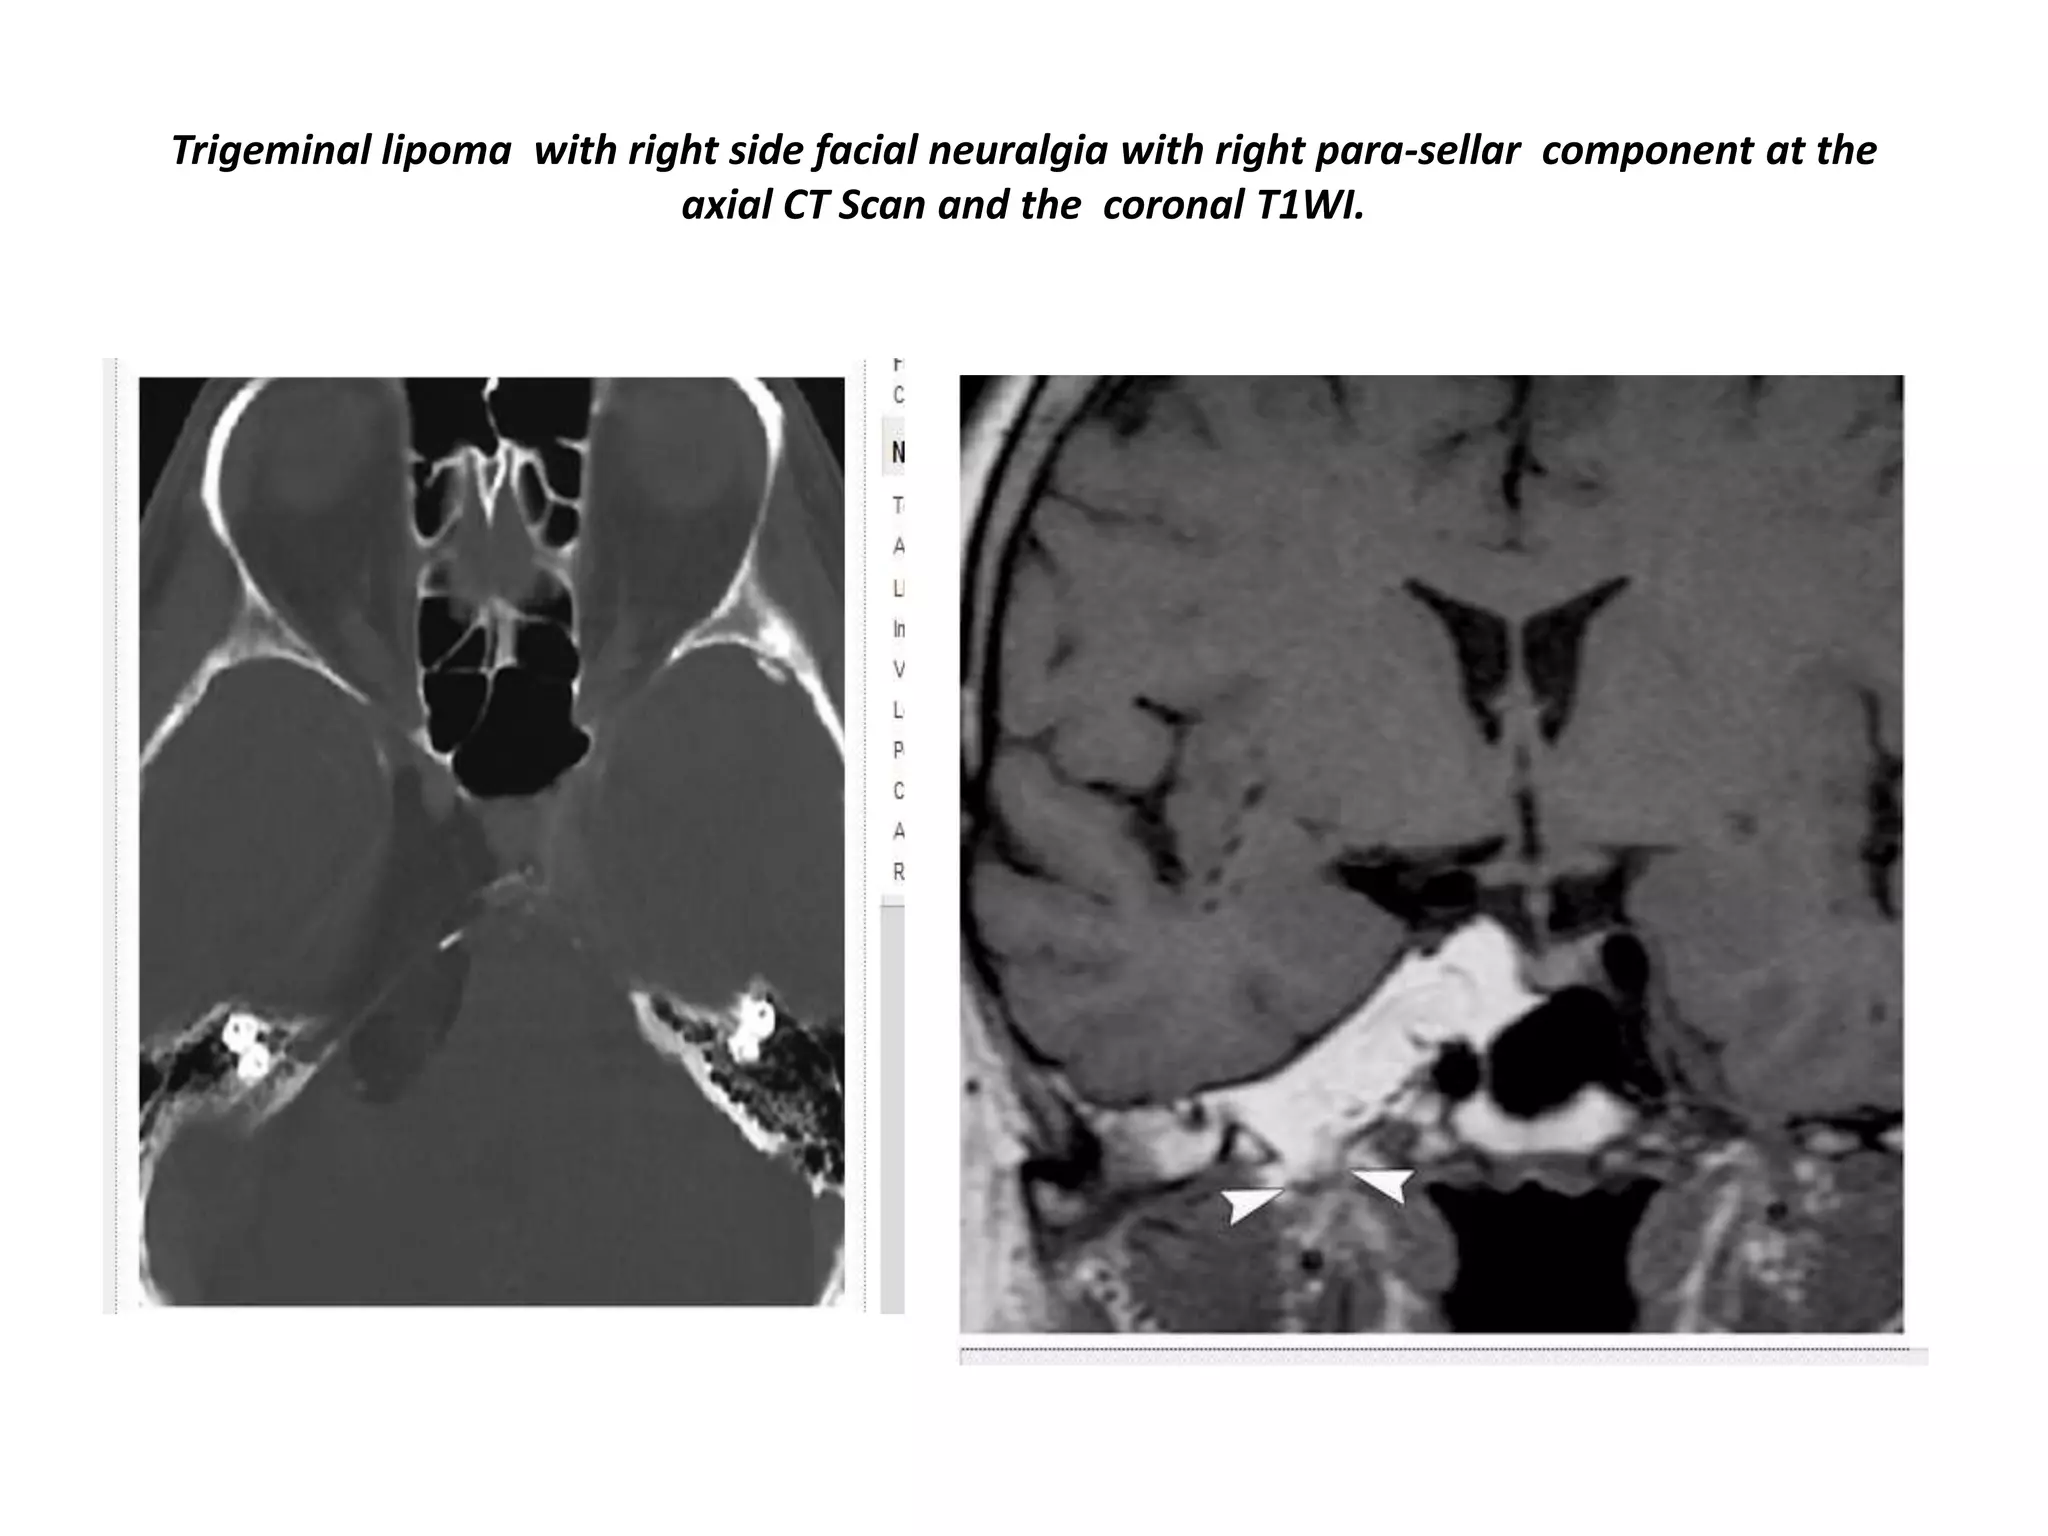

Trigeminal lipoma with right side facial neuralgia with right para-sellar component at the

axial CT Scan and the coronal T1WI.

Trigeminal lipoma withright side facial neuralgia with right para-sellar component at the axial CT Scan and the coronal T1WI.